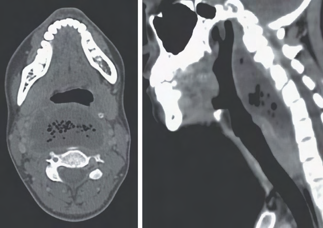

Recent studies indicate that Generative Pre-trained Transformer 4 with Vision (GPT-4V) outperforms human physicians in medical challenge tasks. However, these evaluations primarily focused on the accuracy of multi-choice questions alone. Our study extends the current scope by conducting a comprehensive analysis of GPT-4V's rationales of image comprehension, recall of medical knowledge, and step-by-step multimodal reasoning when solving New England Journal of Medicine (NEJM) Image Challenges - an imaging quiz designed to test the knowledge and diagnostic capabilities of medical professionals. Evaluation results confirmed that GPT-4V outperforms human physicians regarding multi-choice accuracy (88.0% vs. 77.0%, p=0.034). GPT-4V also performs well in cases where physicians incorrectly answer, with over 80% accuracy. However, we discovered that GPT-4V frequently presents flawed rationales in cases where it makes the correct final choices (27.3%), most prominent in image comprehension (21.6%). Regardless of GPT-4V's high accuracy in multi-choice questions, our findings emphasize the necessity for further in-depth evaluations of its rationales before integrating such models into clinical workflows.